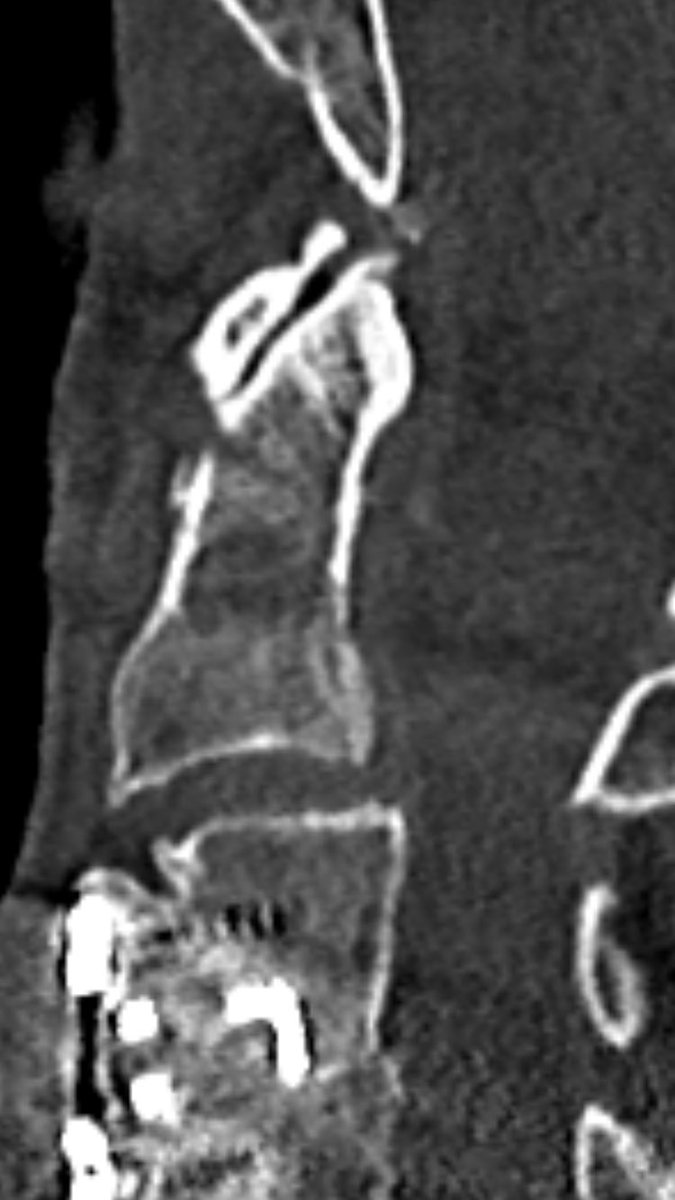

follow up after 8 weeks (l) and 6 month (r) show non-union, as expected. It’s a pseudarthosis.

You can nicely see signs of remodelling, but the fracture line still remains.

after 16 month, remodelling is still ongoing: surprisingly the atlantodental joint is now ankylosed and the fracture line is narrowed, but still not fused.

odontoid fractures type II should not be classified as “unstable”. this patient with his rigid spine was successfully treated without surgery. no severe pain. no severe dislocation. no neurologic deficits.

according to the Panjabi definition of spinal stability, it’s not unstable